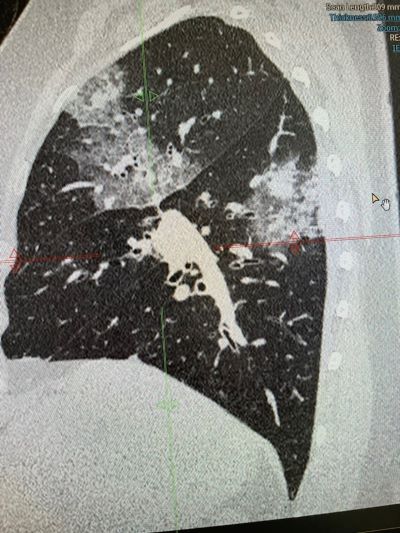

В клинике ВиТерра врачом-рентгенологом, КТ-диагностом было выполнено обследование на спиральном компьютерном томографе.

При исследовании были найдены значительные изменения в лёгочной ткани: на фоне "матового стекла" - выраженные участки консолидации, на фоне которых чётко определяются бронхоэктазы тракционные. Также определяются участки сотового лёгкого и объёмное уменьшение верхней доли справа.

Такие изменения на томограммах свидетельствуют об обычной интерстициальной пневмонии (идиопатический лёгочный фиброз).